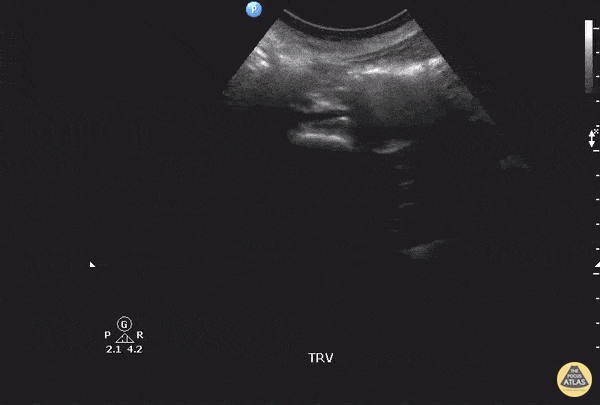

Aorta - Bilateral Iliac Artery Aneurysms

This patient originally complained of right back pain as well as numbness along the thigh and knee. Starting from the abdominal artery, gliding inferiorly will eventually reveal the bifurcation of the abdominal aorta into the left and right common iliac arteries. In this scan, you can see both iliac arteries have enlarged diameters, indicating aneurysms in both. Image courtesy of Robert Jones DO, FACEP @RJonesSonoEM Director, Emergency Ultrasound; MetroHealth Medical Center; Professor, Case Western Reserve Medical School, Cleveland, OH View his original post here